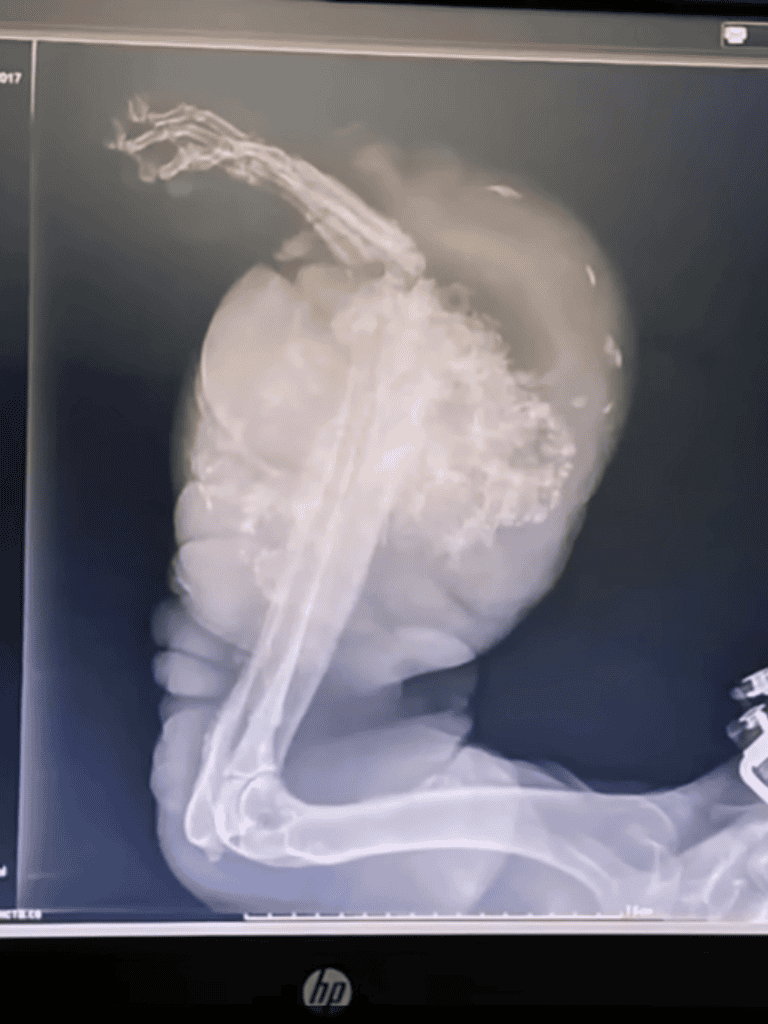

X-rays revealed Jordan had aggressive osteosarcoma, but his lungs were free of metastasis, offering a chance.

Jordan had osteosarcoma, an aggressive bone cancer. The cancer was likely tied to injuries and neglect. His body bore a rapidly growing tumor, symbolizing his hardships.

The veterinarian explained that osteosarcoma is often triggered by trauma. If untreated, it may develop into a malignant tumor. Jordan’s abuse and neglect likely contributed to this condition.

Jordan arrived in Istanbul for surgery. The veterinary team conducted pre-surgery checks, including X-rays, to prepare for the amputation with cautious optimism.